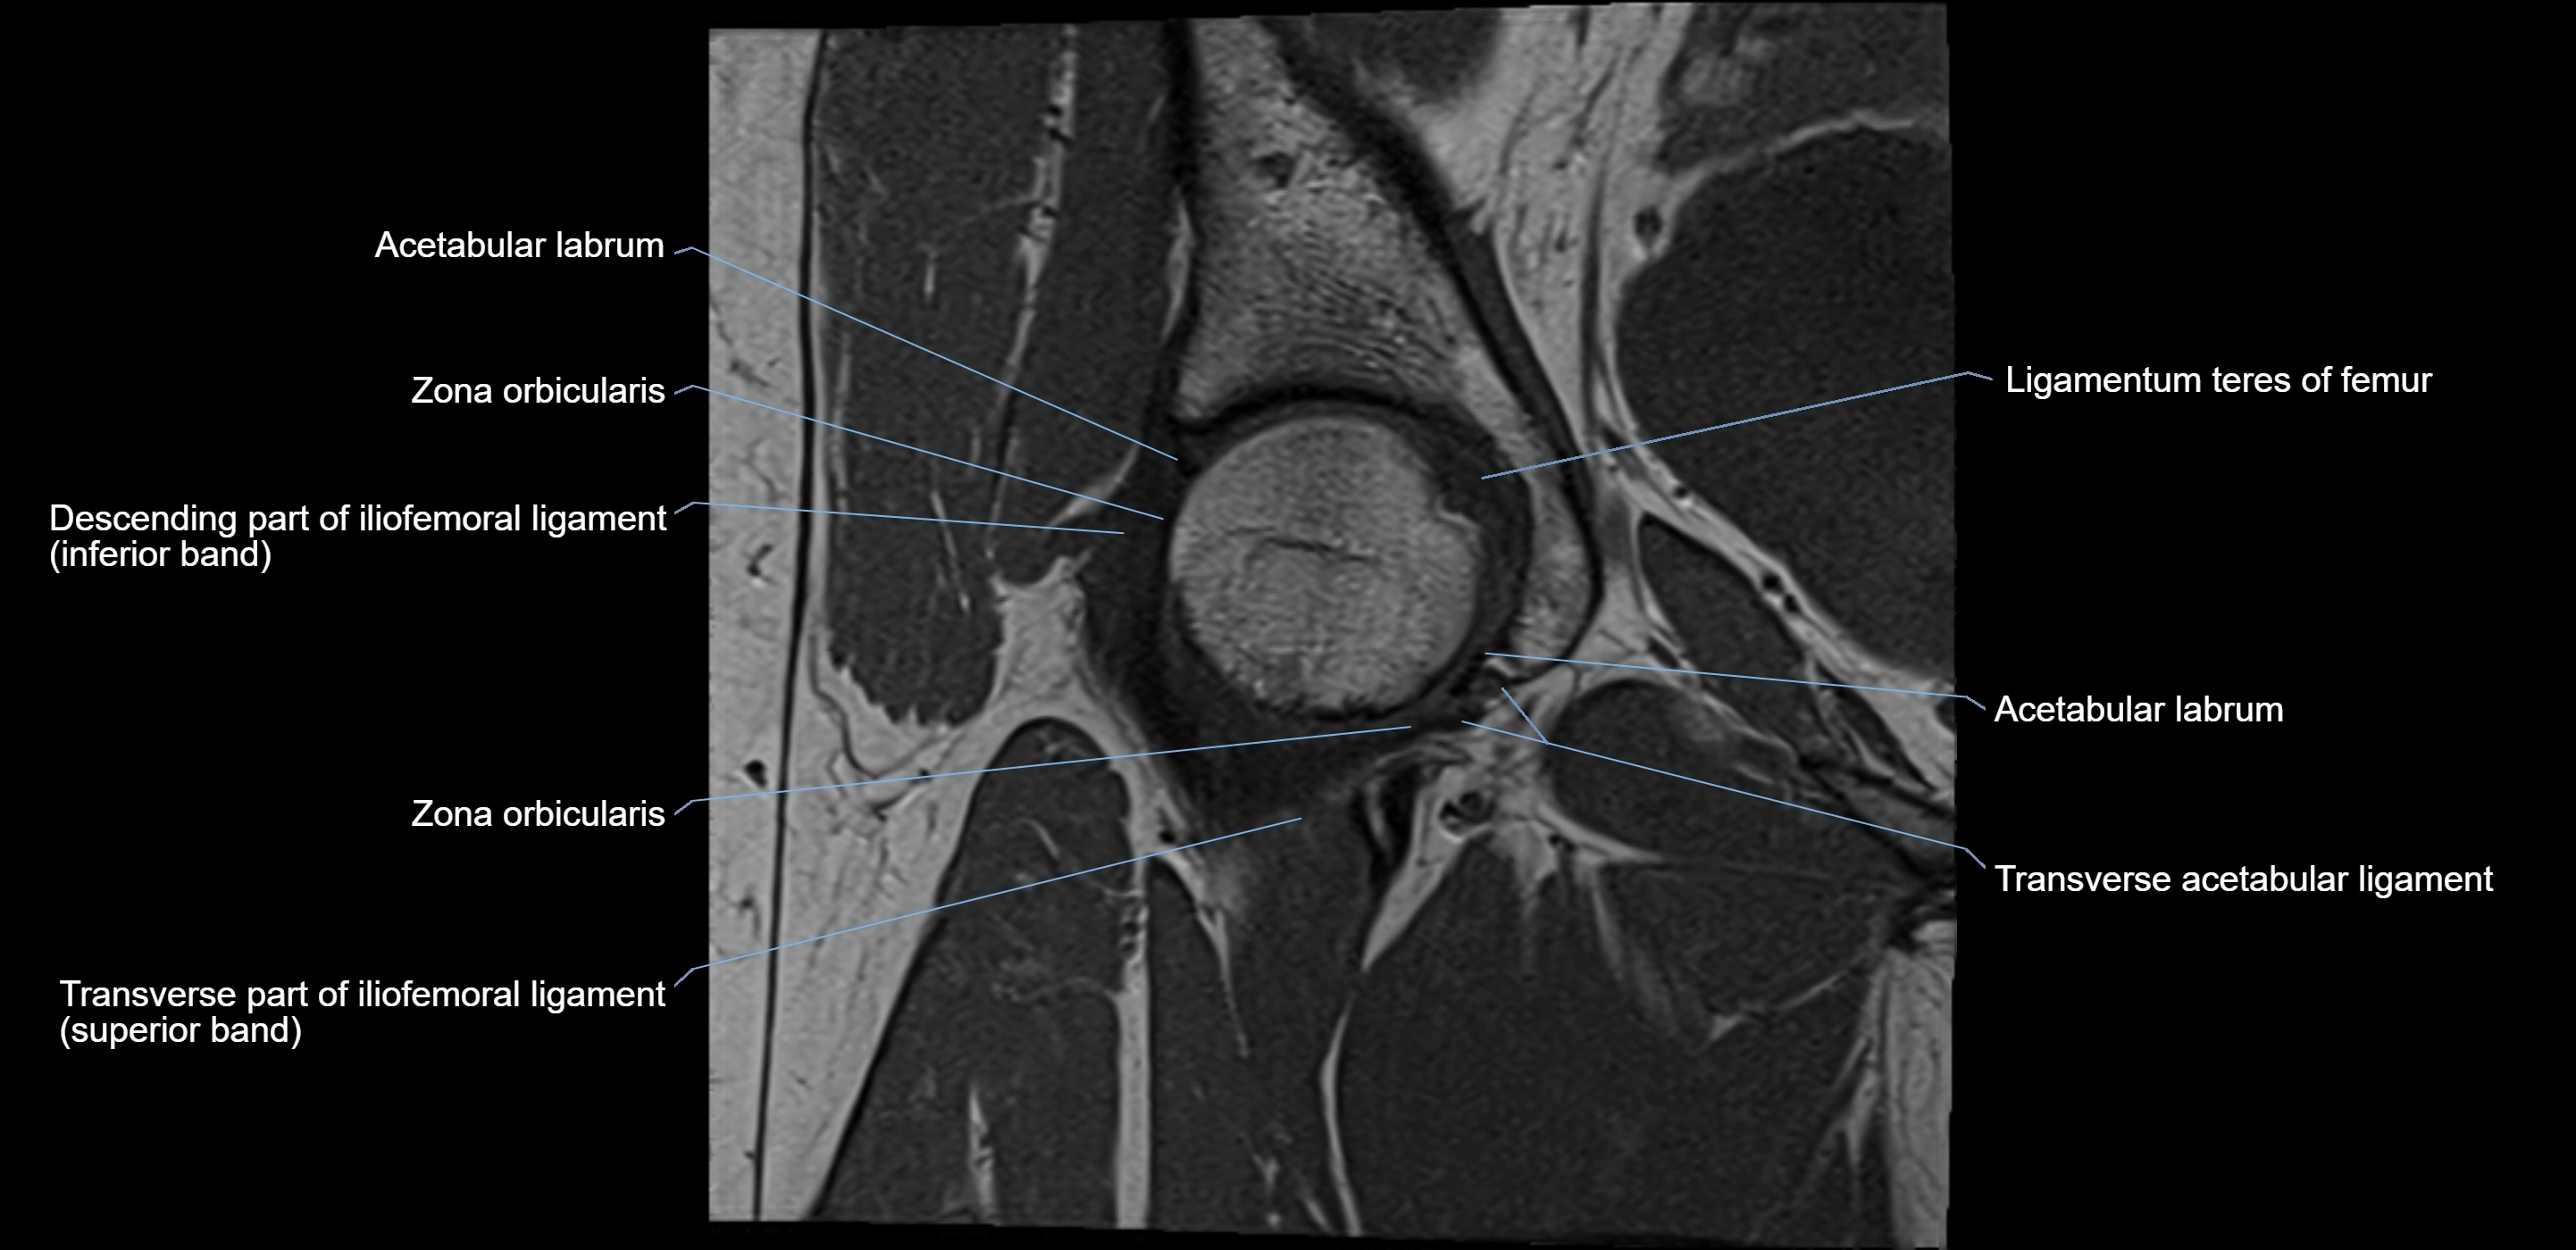

MRI image

image

MRI Appearance

T1-weighted images:

• Labrum: low signal intensity (dark)

• Surrounded by intermediate signal joint fluid (bright on arthrogram)

T2-weighted images:

• Joint fluid: bright, making labral tears visible as fluid extending into or around labrum